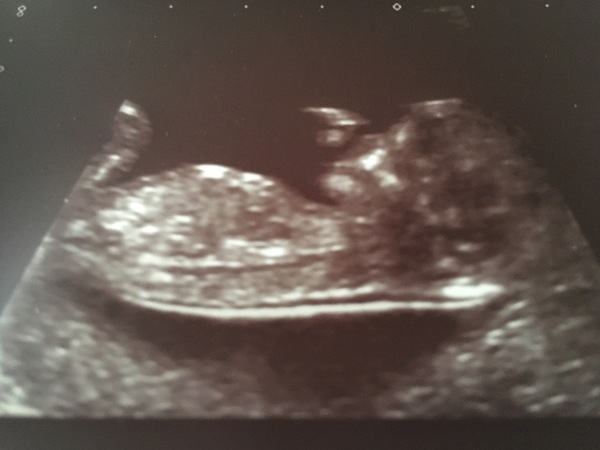

Everything was perfect at our scan. Bang on our dates (4th Feb) 😍

@Fredthespider -lovely little bub x

@Fredthespider Lovely scan 😍 good luck for yours today @hayleyfx

@FredtheSpider lovely scan picture!